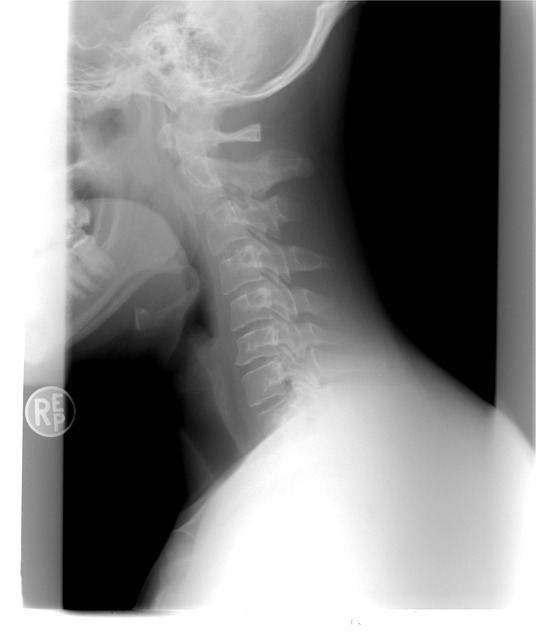

3) 갑상선 목 부음 진단

신체검사:의사는 목 부위를 만져보고 갑상선의 크기와 유형을 평가할 수 있습니다.

갑상선 초음파:갑상선의 크기와 구조, 결절의 유무를 평가합니다.